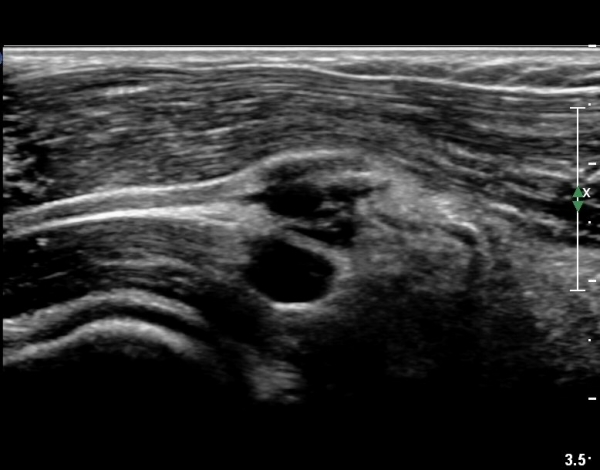

ŽÃËÀÚ¸¦ ¾à°£ ¸»´ÜÀ¸·Î À̵¿ÇÏ´Ï(¿ä°ñµÎ ºÎÀ§) Å« ³¶Á¾ÀÌ º¸ÀÌ°í ³¶Á¾ÀÇ ¿ÜÃø¿¡ Èİñ°£½Å°æÀÇ ¾Ð¹ÚÀÌ °üÂûµÈ´Ù(»çÁø 2). ³¶Á¾Àº ¿ä°ñµÎ¿¡¼­ ¿ä°ñºÎÀ§±îÁö À§Ä¡ÇØ ÀÖ´Ù(»çÁø 3)

ŽÃÊÀÚ¸¦ ȸ¿Ü±Ù ºÎÀ§±îÁö À̵¿ÇÏ´Ï ³¶Á¾Àº °í³ªÂûµÇÁö ¾Ê°í µÎ ȸ¿Ü±Ù »çÀÌ¿¡ Àִ  Èİñ°£½Å°æ

ºÎÁ¾ÀÌ °üÂûµÈ´Ù(»çÁø 4).

Èİñ°£½Å°æ Á¾´Ü¸é°Ë»ç¿¡¼­ ³¶Á¾°ú ÀÎÁ¢ÇÏ¿©  À§Ä¡ÇÑ Èİñ°£½Å°æÀÇ ºÎÁ¾ÀÌ °üÂûµÈ´Ù(»çÁø 5, 6).